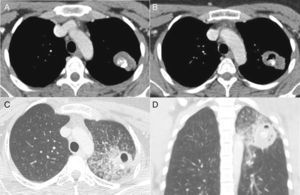

A 28-year-old non-smoking woman presented with an abnormal chest radiograph acquired during a routine check-up. The patient had a history of pulmonary tuberculosis treated 20 years previously. Computed tomography (CT) of the thorax revealed a nodular lesion containing a focal calcification, located in the apicoposterior segment of the left upper lobe (Fig. 1A). The diagnosis of granuloma due to tuberculosis was suggested. The patient refused surgical treatment. The lesion was followed clinically. Eight months after the initial CT examination, the patient was admitted with productive cough, weight loss, and low-grade evening fever. A new CT examination showed cavitation of the previously observed nodule, with adjacent opacities, suggestive of reactivation of the infectious process with bronchial dissemination (Fig. 1B–D). The patient's sputum was positive for acid-fast bacilli and a culture was positive for Mycobacterium tuberculosis.

Chest CT image obtained with the mediastinal window setting (A) shows a nodular soft-tissue lesion with internal calcification located in the apicoposterior segment of the left upper lobe (tuberculoma). CT images obtained with the lung window setting (B–D) 8 months later show cavitation of the nodule associated with focal consolidation, ground-glass opacities, and airspace nodules, indicating reactivation and dissemination of the infection.